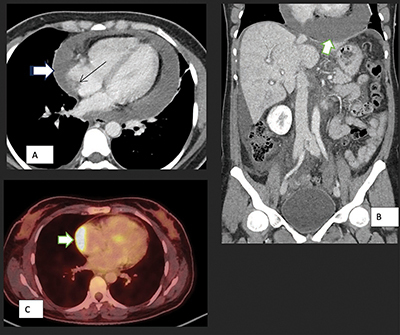

本文讨论了原发性心脏肿瘤的罕见性,尤其是血管肉瘤,占原发性心脏肿瘤的 10%。文章强调了非特异性症状给早期诊断带来的挑战。文章强调了切面成像,尤其是计算机断层扫描(CT)在紧急情况下的重要性。教学要点:尽管原发性心脏肿瘤非常罕见,但放射科医生仍应保持警惕,尤其是出现心包积液时。

This article discusses the rarity of primary cardiac tumors, particularly angiosarcomas, accounting for 10% of primary cardiac neoplasms. The article highlights the challenge of early diagnosis due to nonspecific symptoms. The importance of sectional imaging, particularly computed tomography (CT) scans, in emergent situations is emphasized. Teaching point: Despite the rarity of primary cardiac tumors, radiologists should remain alert, especially when pericardial effusion is present.